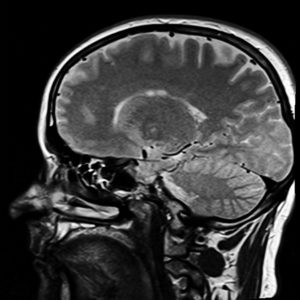

These problems aren’t due to a disc or something that can be seen on MRI.